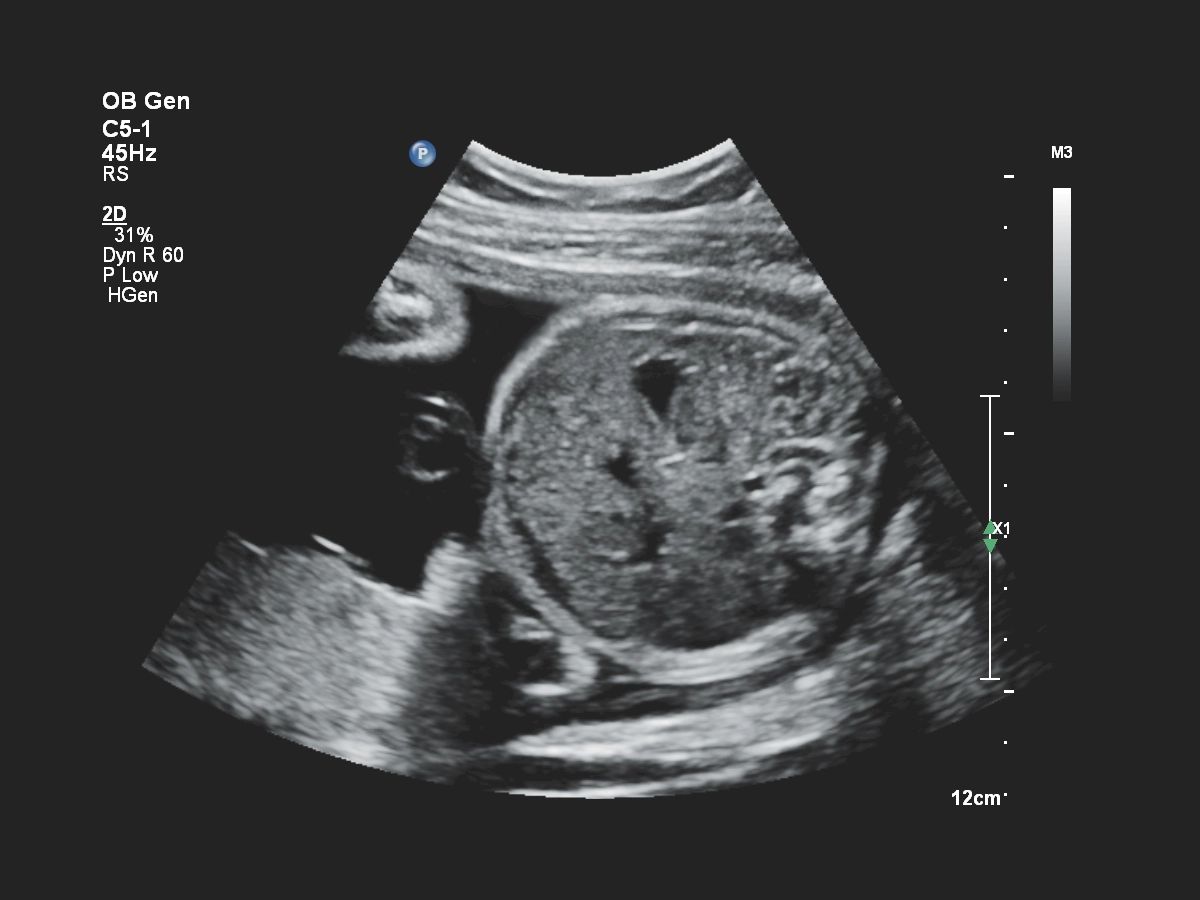

- Акушерство

- Fetal Heart Navigator - функция для навигации сердца плода

Функции для гинекологии и акушерства

- Free Hand 3D - возможность реконструкции 3D изображения при помощи линейного или конвексного датчика

- 4D Imaging - автоматическая визуализация 3D/4D изображения

- TrueVue - виртуальный источник света для получения качественного 3D/4D изображения

- FlexVue - опция для визуализации 3D изображений в плоскости

- aBiometry Assist - автоматические биометрические измерения